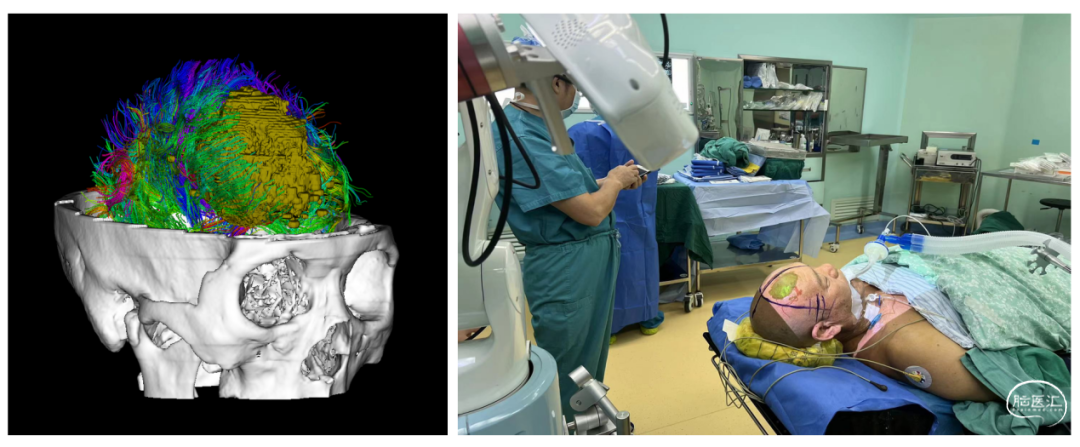

多模态影像评估和引导下脑内肿瘤的精准手术切除及机器人活检,此技术作为微侵袭神经外科的一种精准诠释,它结合了多模态影像评估、精准手术切除和机器人活检等多个方面,为脑内肿瘤的治疗提供了更为精准、安全和有效的手段,这项技术不仅提高了肿瘤的全切率,还降低了手术风险和并发症的发生率,改善了患者的生存质量。同时,机器人活检技术的引入也为脑内肿瘤的病理诊断提供了更为便捷和准确的手段。

胶质瘤是神经外科最常见的颅内原发性恶性肿瘤,其治疗手段包括手术、放疗、化疗、电场治疗等。手术是迄今治疗胶质瘤最有效的手段,但为了巩固手术效果,术后常需要结合放疗、化疗和电场治疗。故此,我院成立胶质瘤专病中心,此专病中心为国家级胶质瘤规范诊疗示范基地,其整合多学科力量,旨在为每位胶质瘤患者带来一种综合、个体化的治疗方案,提高患者的治疗效果和生活质量。